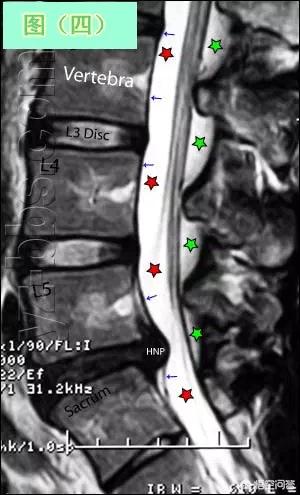

Si un patient souffre d'une hernie discale et souhaite voir l'étendue de la hernie discale et la compression de la moelle épinière et des racines nerveuses dans le canal rachidien, il est nécessaire de procéder à un examen par tomodensitométrie ou par résonance magnétique de la zone correspondante, car seuls la tomodensitométrie et la résonance magnétique permettent de déterminer l'étendue de la hernie discale et de voir plus clairement la compression de la moelle épinière et des racines nerveuses dans le canal rachidien.